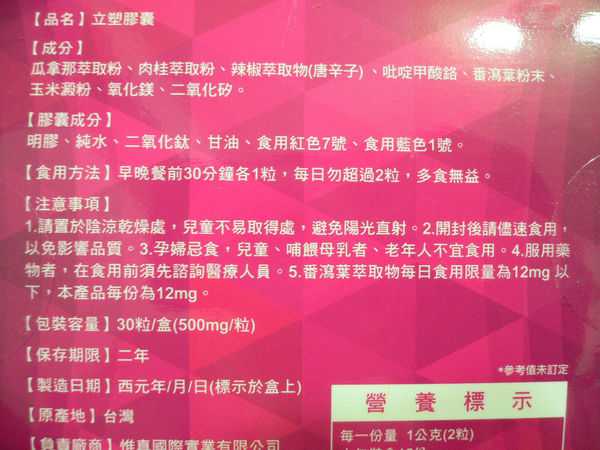

Supercut塑魔纖立塑膠囊的成分有:瓜拿那萃取粉、肉桂萃取粉、辣椒萃取物(唐辛子)、吡啶甲酸鉻、番瀉葉粉末、玉米澱粉、氧化鎂、二氧化矽。

食用方式:早晚餐前30分鐘各1粒,每日不超過2粒。(多食無益)

番瀉葉萃取物每日食用限量為12mg以下,

番瀉葉萃取物每日食用限量為12mg以下,